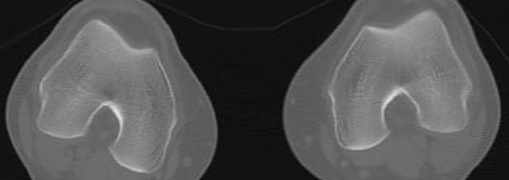

C

Condyles (Arche romaine)

Plateaux tibiaux